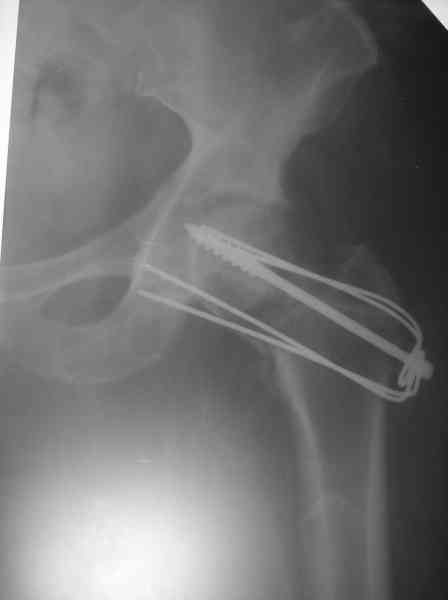

Уважаемый Анатолий Федорович, во-первых, огромное спасибо за прекрасный материал, во вторых, вынужден согласиться с мнением Исмаила. Недавно на форуме один доктор из Тель-Авива привел данные летальности в Израиле 18%! при операциях по поводу перелома шейки. Наверное, летальность подсчитана вместе с установками эндопротезов? Я работаю в Тирасполе (Военный госпиталь РФ) и до ближайшего лечебного учереждения РФ примерно 1000 км, в связи с трудностями на границах снабжения практически никакого. Тем не менее, пытаемся и оперировать шейки, и ещё кое-что по нашим возможностям. К сожалению, косность мышления руководителей здравоохранения не позволяет сделать то, о чем написано в Вашем послании. В гражданском здравоохранении ПМР шейки бедра в настоящее время не оперируются, хотя ребята, которые работают, умеют это делать. Причину, почему они отказываются от операции, я не знаю, поэтому больные доставленые по "скорой" в городскую больницу, потом черз 2-3 недели обращаються ко мне, к обычному синтезу при переломах больше 2-х недель всегда добавляю трансплантат с малоберцовой кости той же ноги.

Где-то с 2001 г. начали оперировать шейки бедра, но теперь так же вынужден отказывать больным - сломался аппарат "Арман". Прооперировали пару больных по Вашему методу (Y-образными спицами). Но потом стали делать примерно так: 2-3 Y-образных спицы нанизывали на мощный винт и дополнительно перегибали ещё в одной плоскости. Затраты и оперативная агрессия примерно та же. Получается довольно жестко. Я Александру Николаевичу отосылал где то 1 год назад патент на изобретение. Прооперированно в настоящий момент 5 больных, к сожалению в 1-ом случае пришлось удалить фиксаторы из-за психоза через неделю после синтеза. В 2-х случаях переломы сраслись конечность опороспособная, в одном случае перегиб винта (к сожалению пришлось испоьзовать вместо винта стержень от аппарата довольно тонкий). А вообще-то эта проблема на уровне городских, ЦРБ, как система лечения не решена, в основном конечно в организационном плане. Хотелось бы, чтоб руководители нашего здравоохранения задумались и конечно внесли бы остеосинтез шейки в стандарты лечения. Посылаю снимок через 3 месяца после синтеза.

> Посылаю снимок через 3 месяца после синтеза.

Не надо проводить фиксаторы в сустав. И при вправлении надо больше вальгизировать.

Спасибо за советы. Да, винты вытачиваем сами."Благоглупости",-уж и помечтать нельзя.Ну а со стандартами так я просто согласился с доктором из С.Посада. Наверное у меня неверные представления о внедрении стандартов на территории РФ. Я живу в таком месте,где вообще неясно по каким законам жить. Российская организация на территории непризнанного гос-ва, с заключением Российской стороной каких то договоров с другим uосударством (Молдовой), присутствия которой у нас не чувствуется. Да, с нижней парой спиц промахнулся. Впрочем это уже случай законченный, нога вполне опороспособна. Кстати, именно эта больная была прооперирована без ортопедического стола.